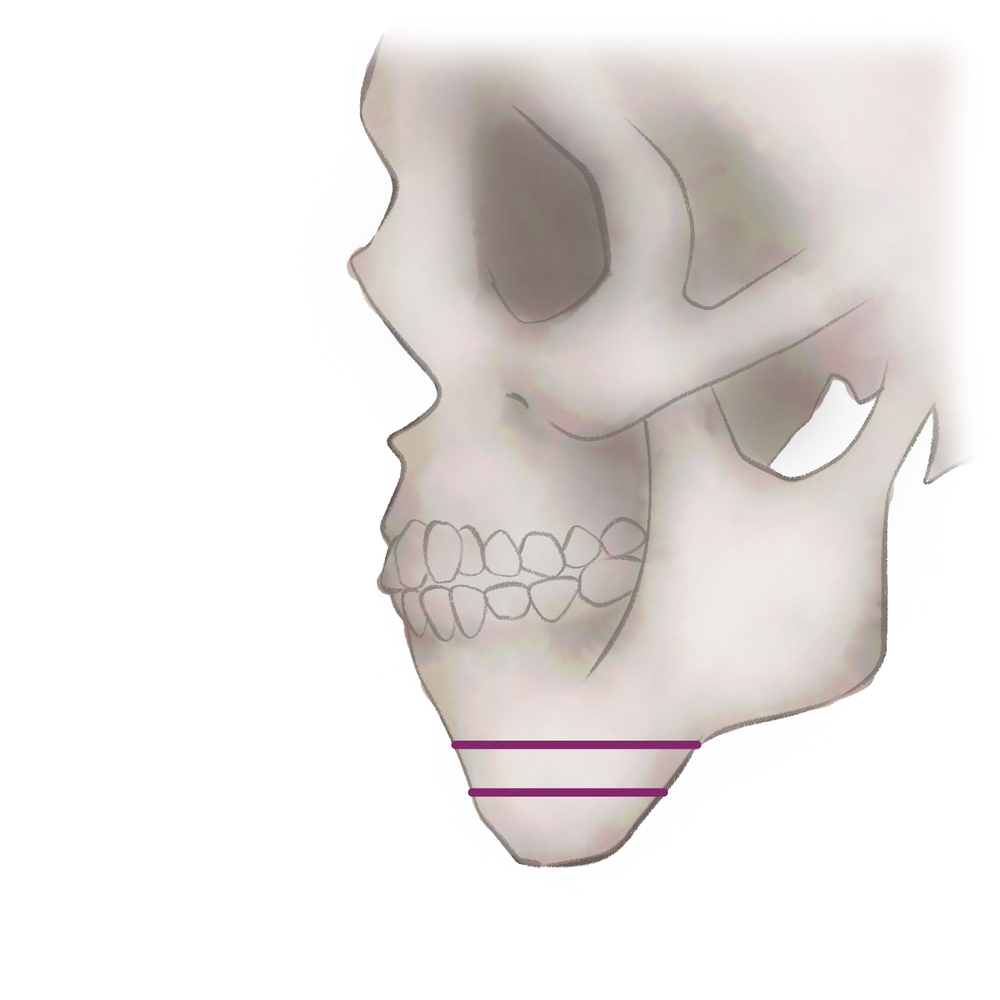

オトガイ骨切り(中抜き)

1.切開線をデザインします

2.骨を切除します

3.骨を移動させ段差を削ります

4.プレートで固定します